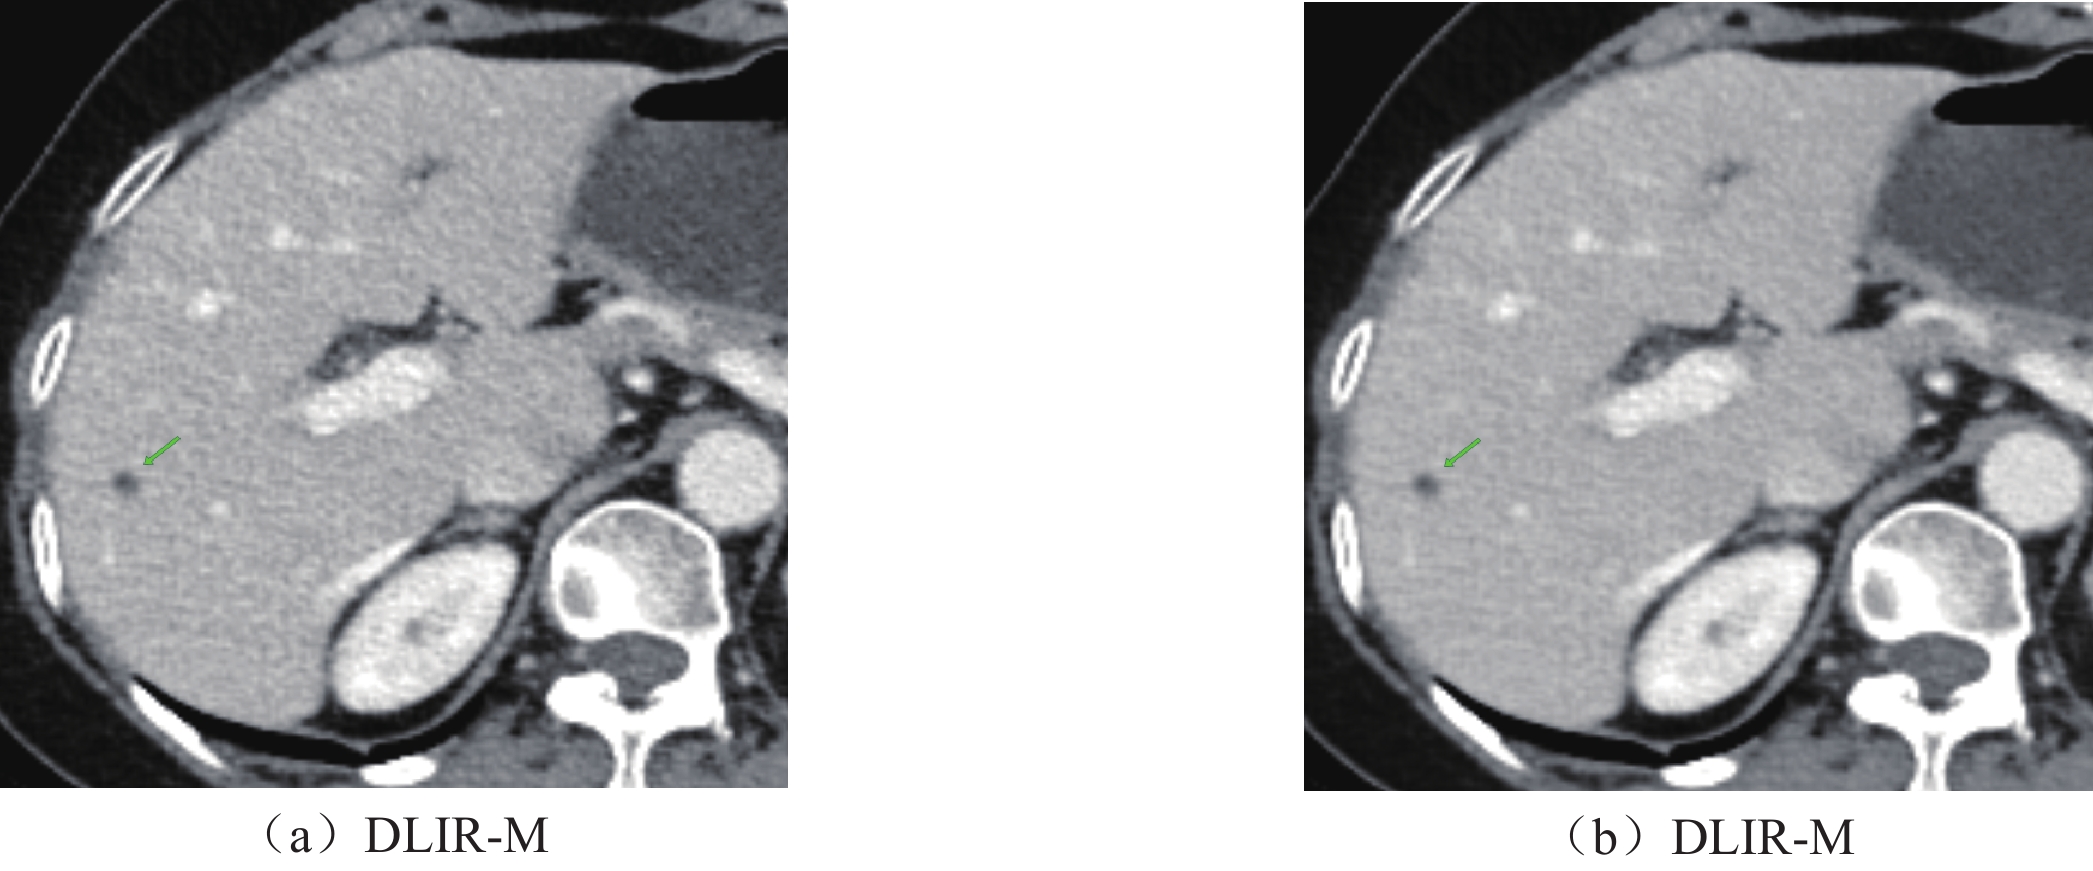

• 摘要: 目的:探讨在肝脏CT增强中结合低辐射剂量和低碘对比剂,深度学习重建算法(DLIR)与自适应统计迭代重建(ASIR-V)的应用效果。方法:前瞻性收集行腹部增强CT的患者82例,随机分成A组和B组,A组(对照组)常规剂量(管电压120kVp,碘对比剂85mL)下门静脉期采用30%、50%、70% ASIR-V(AV30、AV50、AV70)进行图像重建。B组(实验组)双低剂量(管电压80kVp;碘对比剂65 mL)下门静脉期采用中、高强度深度学习(DLIR-M,DLIR-H)进行图像重建。计算了图像噪声(SD)、信噪比(SNR)、对比噪声比(CNR)、病灶对比噪声比(LLR)、品质因数(FOM)、有效辐射剂量(ED)及碘摄入量。两名诊断医生评估不同剂量下不同重建方式的主观图像质量。结果:A组和B组的性别、年龄、体重指数BMI差异均无统计学意义。在有效剂量降低38.40%,对比剂用量降低23.53%下,DLIR-M与AV50、DLIR-H与AV70肝实质、门静脉SD值差异均无统计学意义,肝实质、门静脉SNR中仅DLIR-M与AV50不具有统计学意义,肝实质、门静脉CNR中仅DLIR-M与AV70差异无统计学意义,病灶对比噪声比(LLR)与品质因数(FOM)中,仅DLIR-M与AV70差异无统计学意义。在各项主观图像质量评估中,双低剂量下的DLIR表现优于常规剂量的AVIR-V,尤其是DLIR-H表现最佳。结论:与常规剂量下ASIR-V相比,DLIR在“双低”(低辐射剂量低对比剂)剂量下可以提高图像质量和肝脏低对比度病灶的检测能力。

Abstract: Objective: Exploration of the application of a deep-learning reconstruction algorithm (DLIR) and adaptive statistical iterative reconstruction (ASIR-V) based on the combination of low radiation dose and low iodine contrast agent in liver CT enhancement. Methods: A total of 82 patients who underwent abdominal enhanced CT were prospectively selected and randomly separated into groups A and B. Group A (control group) received a conventional dose (tube voltage 120 kVp; iodine contrast 85mL) and inferior portal image reconstruction was applied using 30%, 50%, and 70% ASIR-V (AV 30, AV 50, AV 70). In Group B (experimental group), image reconstruction was based on medium- and high-intensity deep learning (DLIR-M, DLIR-H). Image noise (SD), signal-to-noise ratio (SNR), contrast-to-noise ratio (CNR), lesion contrast-to-noise ratio (LLR), quality factor (FOM), effective radiation dose (ED), and iodine intake were calculated. Subjective image quality results were obtained for different reconstruction methods at different doses. No significant differences in gender, age, and BMI between groups A and B were found. For 38.40% effective dose and 23.53% reduction in the contrast agent dosage, no significant SD differences were found between DLIR-M and AV 50, DLIR-H and liver parenchyma and AV 70. Only DLIR-M and AV 50 in the portal SNR were not statistically significant. No significant differences were found between DLIR-M and AV 70 in liver parenchyma and portal CNR. Concerning LLR and FOM, no significant differences were found between DLIR-M and AV 70. For various subjective image quality assessments, DLIR at double low doses outperformed AVIR-V, especially DLIR-H. Conclusions: DLIR can improve image quality and the ability to detect liver low contrast lesions at “double low” (low radiation dose low contrast) compared to ASIR-V.